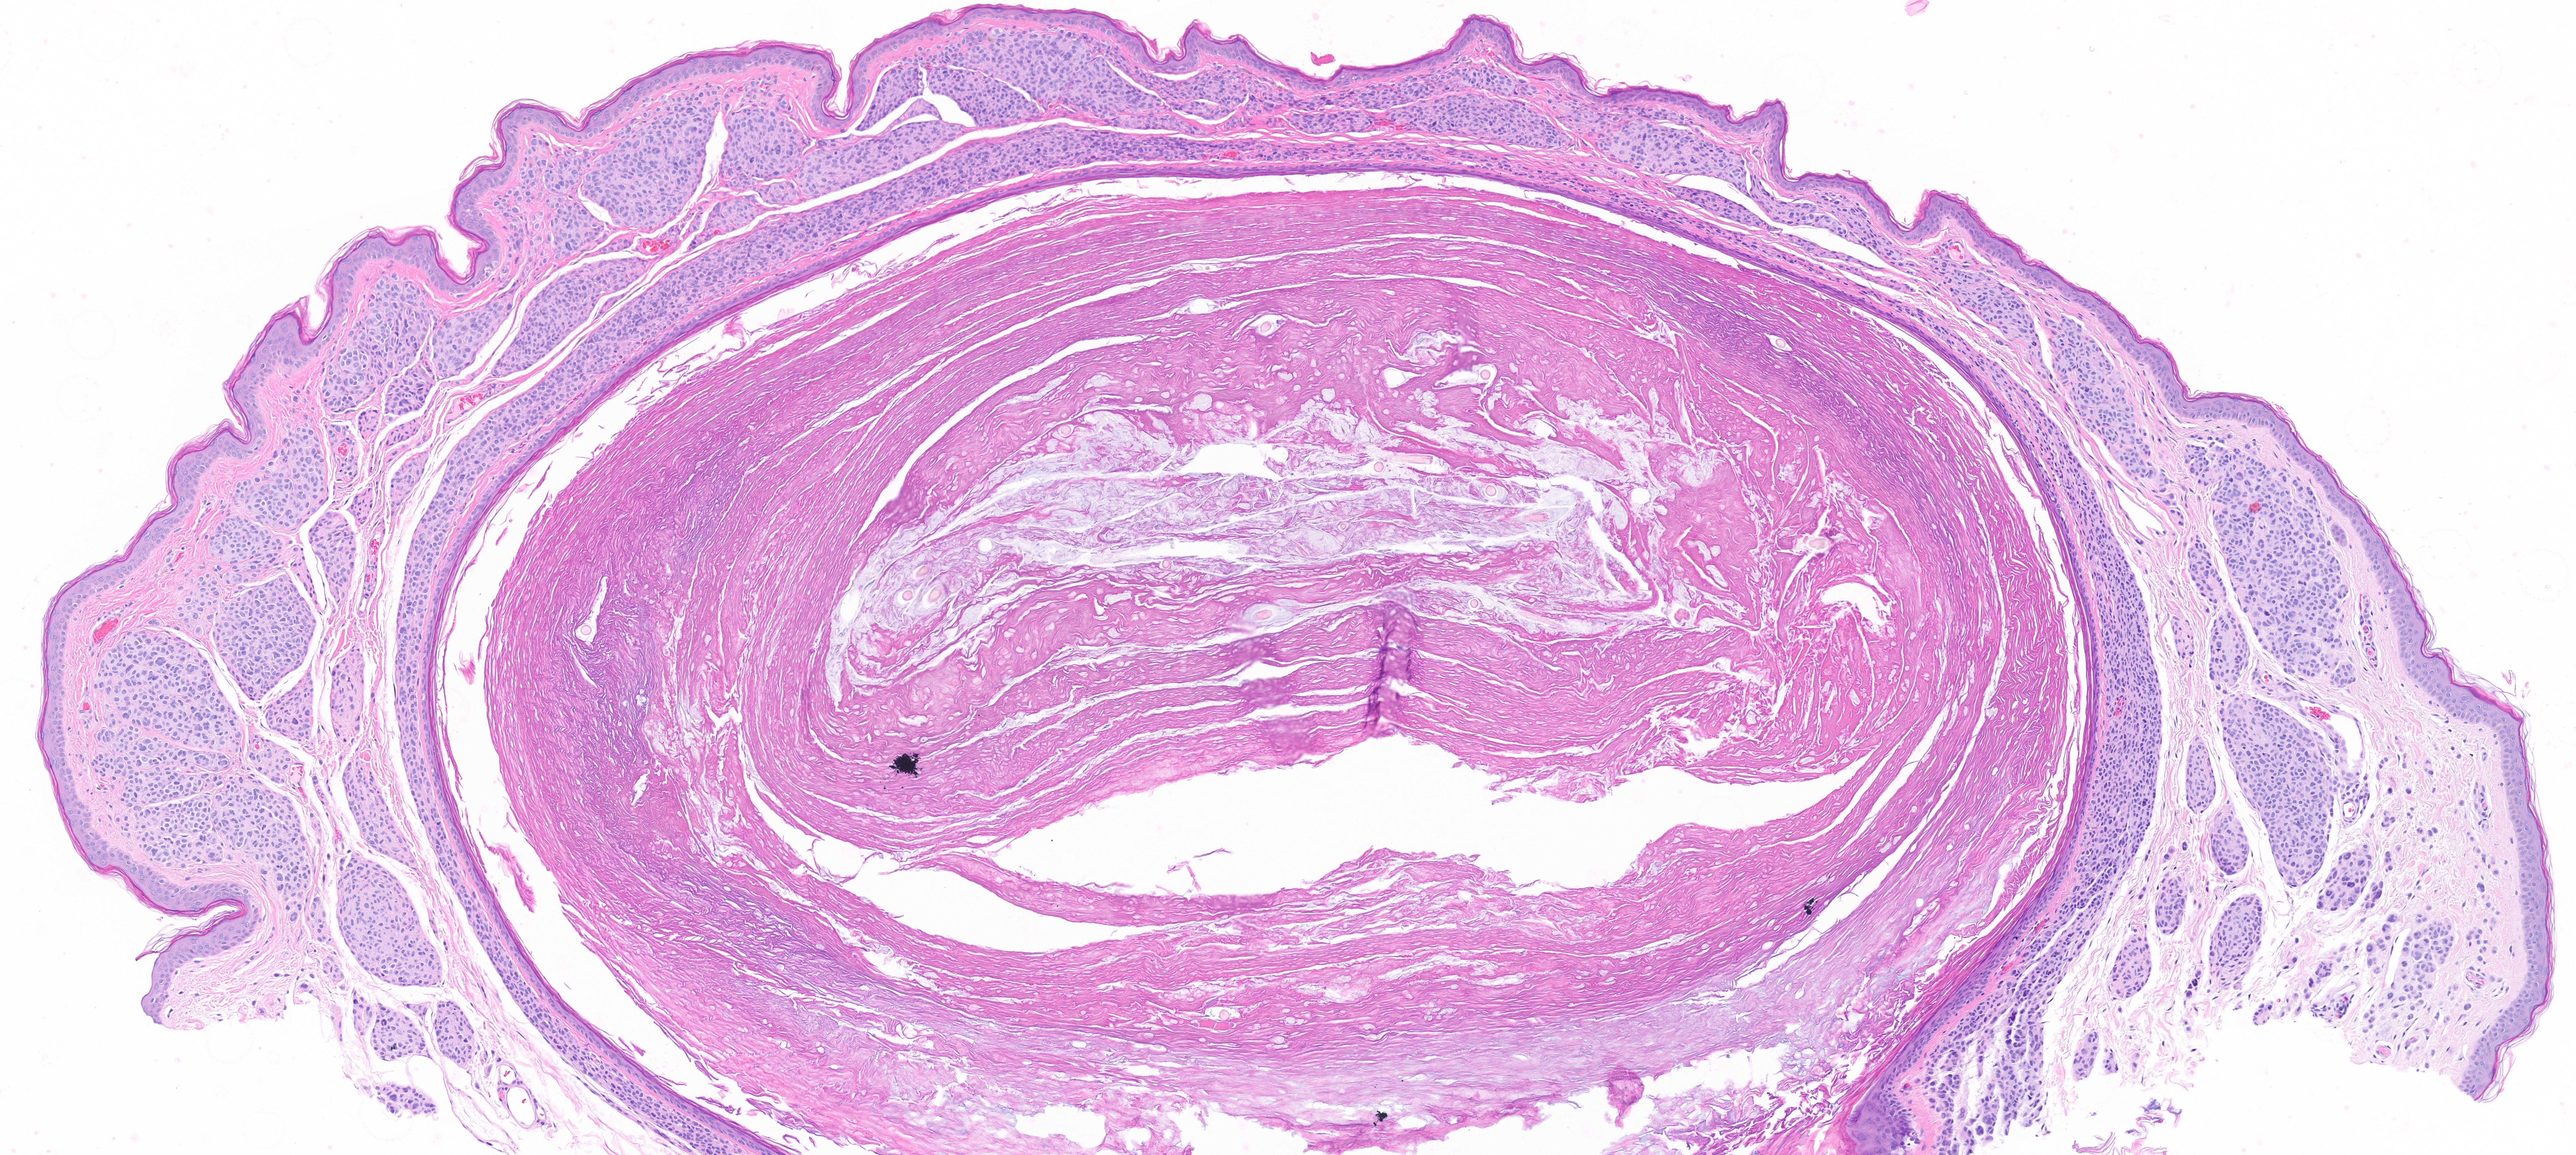

Expert microscopic examination of skin tissue serving dermatologists across Indiana and the Midwest with guaranteed 24-hour turnaround for routine cases.

Nail & hair pathology

and more...